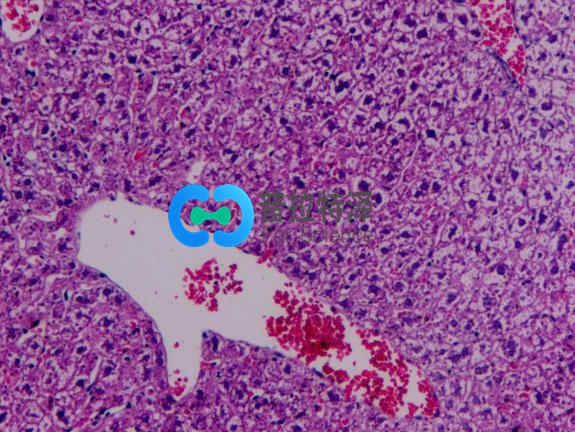

光鏡觀察:

正常組肝小結(jié)構(gòu)正常,肝細(xì)胞以中央靜脈為中心呈放射狀排列。無肝細(xì)胞腫脹及脂肪變性。模型組肝組織HE染色顯示:造模4周后大鼠肝臟即有輕微的肝細(xì)胞脂肪變性,標(biāo)本還出現(xiàn)匯管區(qū)及小葉內(nèi)炎癥細(xì)胞浸潤和散在的點狀壞死;造模8周大鼠多呈中度脂肪變,且炎癥活動積分明顯高于造模4~8 周大鼠,可見到小葉內(nèi)炎癥,炎癥細(xì)胞主要以單核細(xì)胞為主,炎癥程度明顯加重;造模 18周大鼠呈中重度的大泡性脂肪變,脂滴分布密度通大,可見大部分旺細(xì)胞漿含大脂滴,部分脂滴形成大空泡。將細(xì)胞核擠壓至一邊,目以中央靜脈周圍為其:肝小葉結(jié)構(gòu)破壞,肝細(xì)胞排列不規(guī)救,并伴大量肝細(xì)胞腫脹,部分呈氣球樣變,匯管區(qū)炎癥尚輕微。